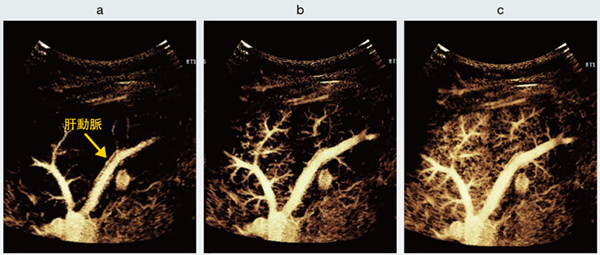

図1 正常肝実質のSuper Resolution MVI画像

門脈の末梢が精緻に描出されており,門脈に並走する肝動脈も明瞭に分離して観察される。肝実質が時間の経過とともに規則的かつ均一に染まり,正常な肝血流動態を反映している。

a:Flash後1秒 b:Flash後3秒 c:Flash後7秒